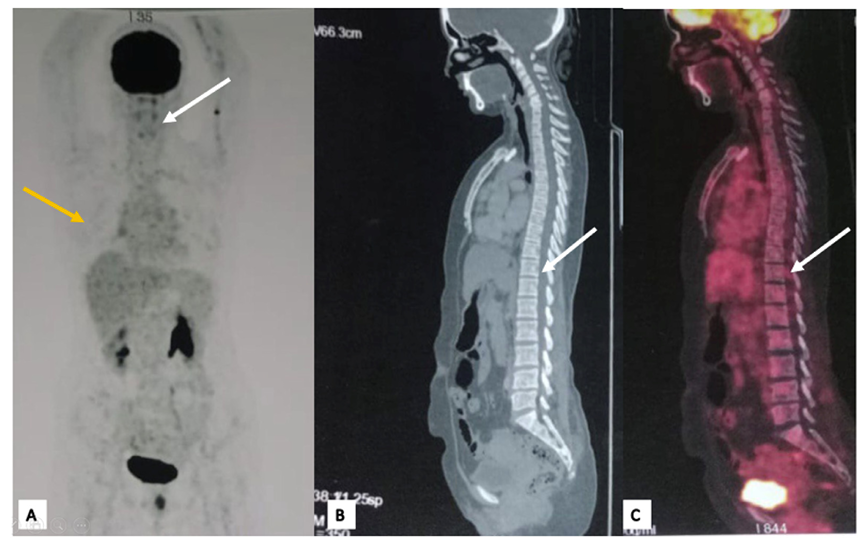

乳腺彩超:于12点方向见边界不清、形态不规则的低回声区,彩色多普勒及微血管成像未见内部血流。结合影像学表现,病灶评为BI‑RADS 4B类,恶性中度可疑(10%-50%)。双侧腋窝及对侧乳腺未见异常。

图4 病灶彩超

在超声引导下行穿刺活检,病理示ILC,ER阳性、PR阳性、HER2状态待定,Ki‑67指数约8%-10%。